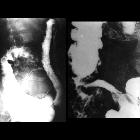

Fluoroscopy

Features on barium small bowel follow-through include:

- mucosal ulcers

- aphthous ulcers initially

- deep ulcers (>3 mm depth)

- longitudinal fissures

- transverse stripes

- when severe leads to cobblestone appearance

- may lead to sinus tracts and fistulae

- widely separated loops of bowel due to fibrofatty proliferation (creeping fat)

- thickened folds due to edema

- pseudodiverticula/pseudosacculation formation: due to contraction at the site of ulcer with ballooning of the opposite (usually antimesenteric) site

- string sign: tubular narrowing due to spasm or stricture depending on the chronicity